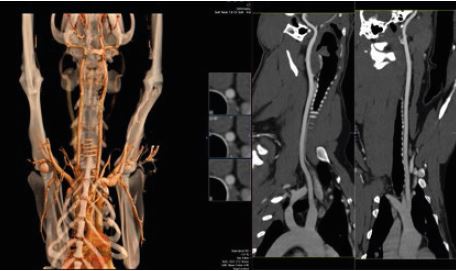

КТ-ангіографія

Чутлива технологія управління контрастом забезпечує стабільно високу якість результатів для діагностики різних судинних захворювань. Технологія SEMAR (Single Energy Metal Artifact Reduction) від Canon Medical мінімізує артефакти від металу та покращує візуалізацію імплантатів, опорної кістки та прилеглих м'яких тканин. Передові технології Canon Medical для комп'ютерного томографа Aquilion включають методи адаптивного ітеративного зменшення дози 3D (AIDR 3D) та вдосконалену інтелектуальну реконструкцію з глибоким навчання Clear-IQ Engine (AiCE) (DLR). Ця виняткова реконструкція на основі штучного інтелекту значно знижує рівень шуму і підвищує SNR (співвідношення сигналу до шуму).